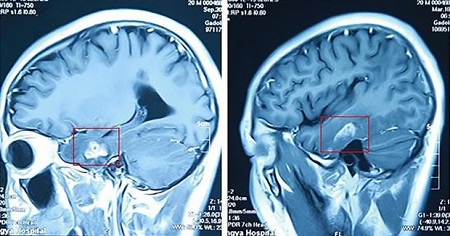

Kí sinh trùng dài 11cm sống trong não của nam thanh niên. |

Các bác sĩ đã phát hiện có ấu trùng sinh sống trong não khi siêu âm. |

Các vết cắt chi tiết trên đầu của anh cho thấy anh đã bị nhiễm trùng sán dây.

Con sâu này dài 11 cm (4,33 inch).